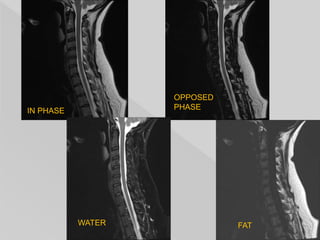

 in-phase = (water + fat)

 opposed-phase = (water - fat)

 fat only = in-phase - opposed phase

= (water + fat) - (water - fat)

 water only = in-phase + opposed phase

= (water + fat) + (water - fat)

 The water only image can be used as a fat-

suppressed image.

 The fat only image can then be combined

with other sequences of various weightings

to give fat suppression. It can also be used

for quantification in certain scenarios.

IN PHASE

OPPOSED

PHASE

WATER FAT